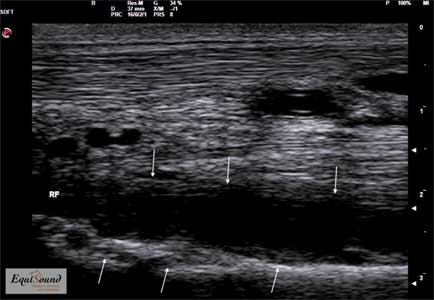

Chez le cheval, les tendons fréquemment sujets au développement de foyers dégénératifs sont par exemple le suspenseur du boulet et le tendon fléchisseur profond (photos 1 et 2). Chez le chien, le tendon d’Achille (ou corde du jarret) (photo 3) et le fléchisseur ulnaire du carpe (photo 6) sont parfois sujets à une pathologie chronique.

Image échographique en vue longitudinale de l’insertion distale du tendon d’Achille chez un chien présentant une lésion dégénérative d’évolution chronique. (La région proximale est à gauche, la région distale à droite)